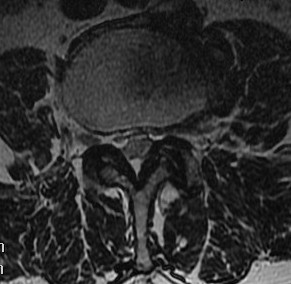

B. Axial slices

Findings

- no fat about dura

- trefoil shape canal

- lateral recess or foramina compression

- nerve root compression